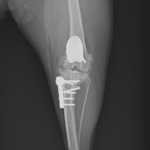

膝蓋骨内方脱臼+前十字靭帯断裂 PGR#21+CBLO #251

過去に膝蓋骨内方脱臼G4で手術を受けている患者さんが、急に跛行を呈するようになったとの事。関節炎が顕著であり、前十字靭帯断裂の併発も疑われます。ファットパッドサイン陽性、脛骨圧迫試験陽性、脛骨ピボット圧迫試験陰性でした。大腿骨滑車のリプレイスメントとCBLOで対応しました。